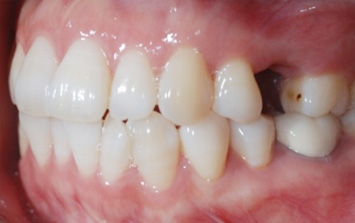

오른쪽 앞니 상실로 내원한 환자분. 앞니의 상실로 치아 사이 틈이 넓어지고 있어 교정으로 임플란트 식립 공간을 만든 후

임플란트 식립을 하였습니다. 앞니가 상실된 기간이 길어 교정치료를 하지 않고 임플란트를 식립할 경우

벌어진 치아 사이로 음식물이 끼거나 치아형태 이상으로 문제가 생길 수 있습니다.